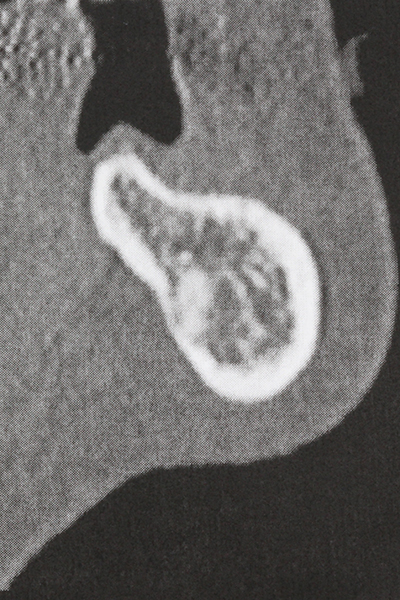

La piezochirurgia presenta altri vantaggi per quanto riguarda la raccolta di blocchi ossei. Oltre all'elevata precisione dell'osteotomia appena descritta, l'utilizzo di puntine per sega molto sottili permette di minimizzare in maniera significativa la perdita di materiale. È molto probabile che si verifichi una maggiore perdita di materiale durante la raccolta utilizzando puntine di strumenti più spessi, in particolare delle frese Lindemann (Lakshmiganthan, Gokulanathan et al. 2012). La separazione basale, necessaria in particolare per i trapianti di blocchi nella zona retromolare, viene semplificata grazie a seghe specificatamente progettate di forma rettangolare; di conseguenza la piezochirurgia è considerata una procedura precisa, semplice e sicura per la raccolta di blocchi di osso nella zona retromolare (Happe 2007) (figg. 1-12).